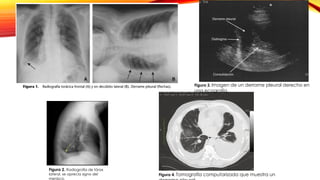

Figura 2. Radiografía de tórax

lateral, se aprecia signo del

menisco.

Figura 3. Imagen de un derrame pleural derecho en

una ecografía.

Figura 4. Tomografía computarizada que muestra un

Diagnóstico y exámenes complementarios Pruebas imagenológicas Radiografíade tórax PA y lateral El volumen de líquido del espacio pleural debe ser ˃ 250 ml para que se pueda ver en la radiografía de tórax Hay borramiento del ángulo costofrénico en la Rx posteroanterior de tórax. La imagen más típica de derrame pleural es la presencia de una opacidad homogénea de borde cóncavo superior . Ecografía torácica Es la prueba más sensible para detectar derrame pleural Muy útil para detectar formas atípicas, como los derrames loculados o encapsulados Tac de tórax Ofrece una caracterización mucho mejor de las alteraciones pleurales y parenquimatosas Distingue entre atelectasia y derrame, y diferencia los derrames tabicados de los abscesos pulmonares u otros procesos parenquimatosos Más atípicas: Elevación de un hemidiafragma en el derrame subpulmonar o la opacificación de todo un hemitórax con desplazamiento contralateral del mediastino ante un derrame masivo.

Figura 2. Radiografíade tórax lateral, se aprecia signo del menisco. Figura 3. Imagen de un derrame pleural derecho en una ecografía. Figura 4. Tomografía computarizada que muestra un